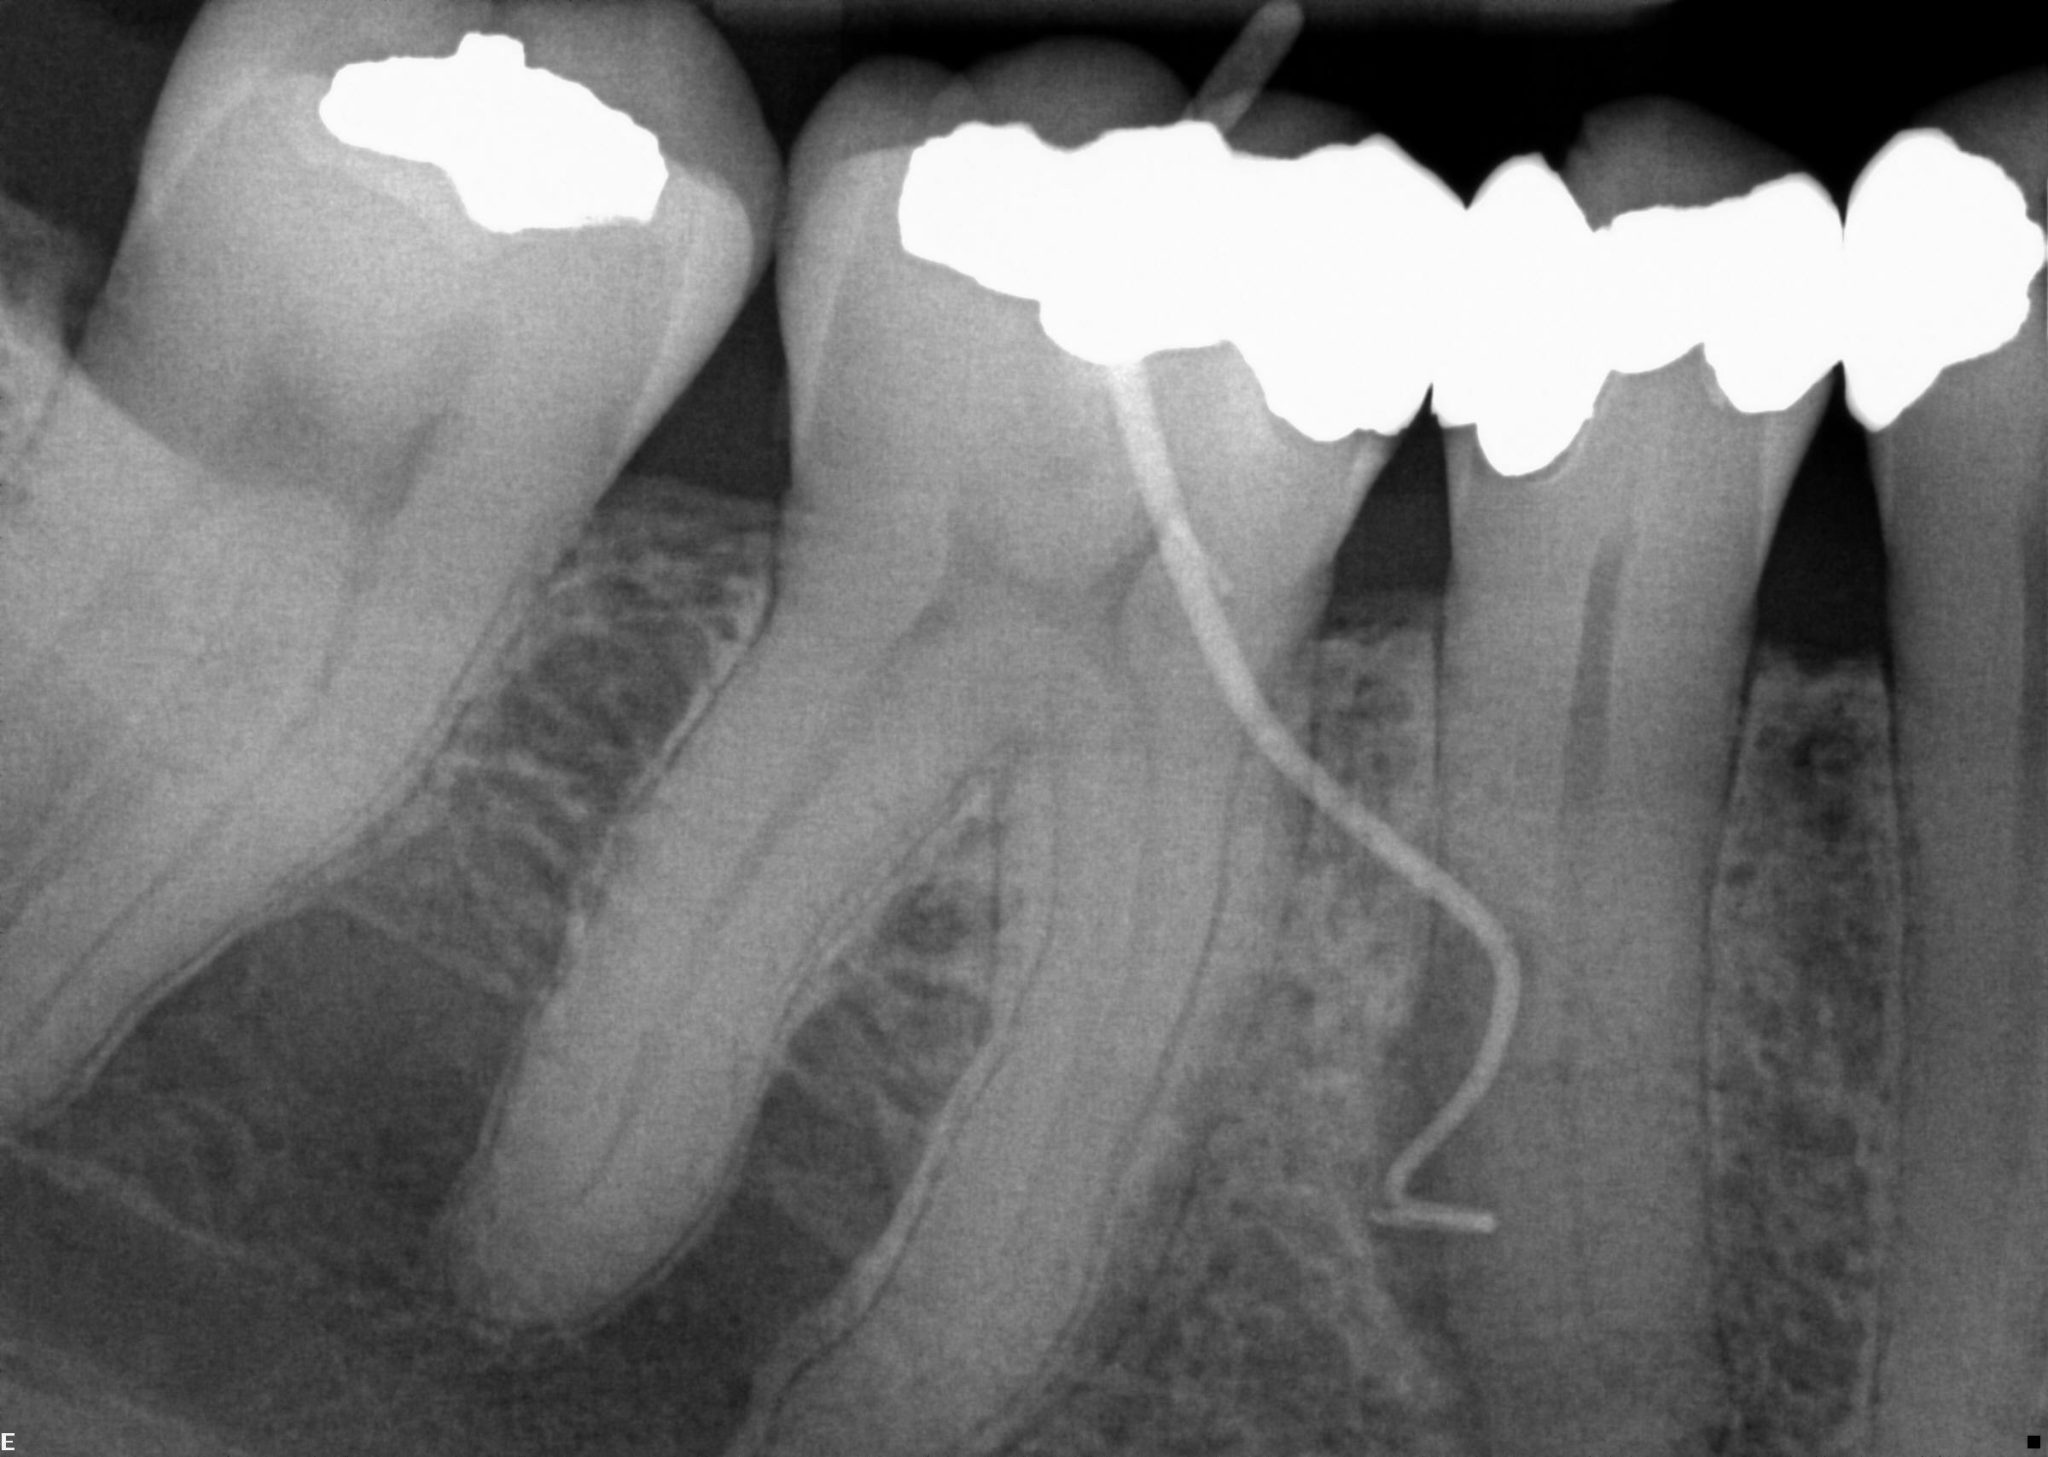

Root canal treatment (also know as endodontic therapy) is necessary. Also known as endodontic treatment, root canal therapy. Should a tooth fail or heal properly or become reinfected after a root canal, endodontic retreatment at mint can help restore its health. Our specialty is getting people to love going to the dentist, and because of our mint difference, they do. Our clinic, based conveniently in central south east london, mint dental, offers the best in root canal therapy and treatments for. Mariana mintcheva, mit der dein. Our talented staff at mint dentistry conducts a number of general, corrective, restorative, and cosmetic dentistry procedures, in addition to. Erlebe deine zähne neu mit der zahnästhetik von mint by dr. Endodontics root canals can save a badly damaged or infected tooth.